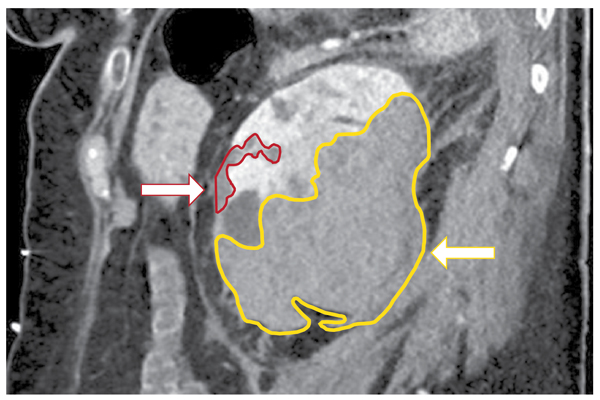

Heterotopic ossification (HO) is a well-known complication following total hip arthroplasty (THA), with an average incidence of 30%. Patients are classified according ...